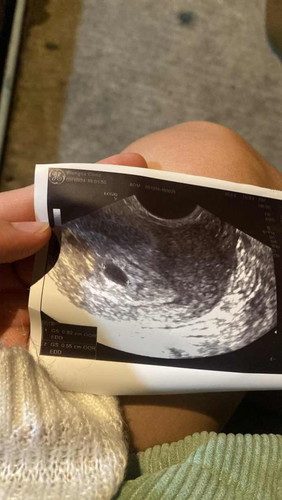

ตอนนี้4สัปดาห์5วัน มีเลือดน้ำตาลคล้ำออกมาตั้งแต่เมื่อวาน ไปซาวมาเจอถุงตั้งครรภ์ หมอนัดอีกที3อาทิตย์เลยค่ะ